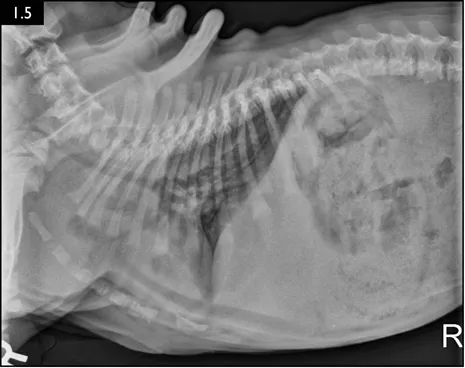

Clinical signs can be strongly suggestive of bacterial pneumonia, but radiographs are important for confirmation, to characterize the disease (and potential etiology) and to provide a baseline for monitoring response to treatment (Figs. 1.4–1.6). A lag between clinical signs and radiographic changes can occur, and initial radiographs may be normal or appear discordant with clinical severity.

Fig. 1.5 Radiograph showing severe tracheal narrowing and concurrent bronchoalveolar pneumonia in a bulldog puppy with severe respiratory compromise. (Courtesy of Atlantic Veterinary College)